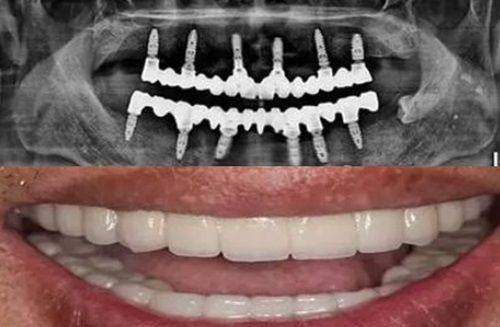

北京品阁口腔门诊部拥有一支专精的医生团队。这些医生都具备丰富的临床经验和扎实的专精知识。他们毕业于有名口腔院校,经过严格的专精培训,在牙齿矫正、牙齿修复、种植牙等多个领域都有深入的研究和出色的技术。

在治疗过程中,医生们会根据患者的具体情况,制定个性化的治疗方案。比如,对于牙齿不齐的患者,医生会通过详细的口腔检查和数据分析,选择更适合患者的矫正方式,确保矫正成效达到至佳。而且,医生们还会耐心地解答患者的疑问,让患者清楚了解治疗过程和注意事项,消除患者的顾虑。